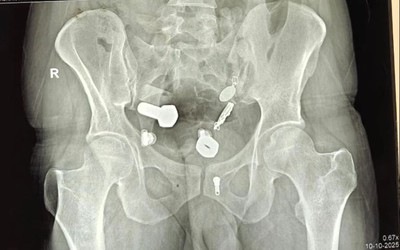

Người đàn ông đau bụng đi khám, bác sĩ phát hiện "bí mật" bên trong

Các bác sĩ đã lấy ra đồng hồ đeo tay và các vật dụng khác như thanh kim loại, đinh sắt, ghim, đai ốc, bu lông và ba mặt dây chuyền từ bụng của một người đàn ông.